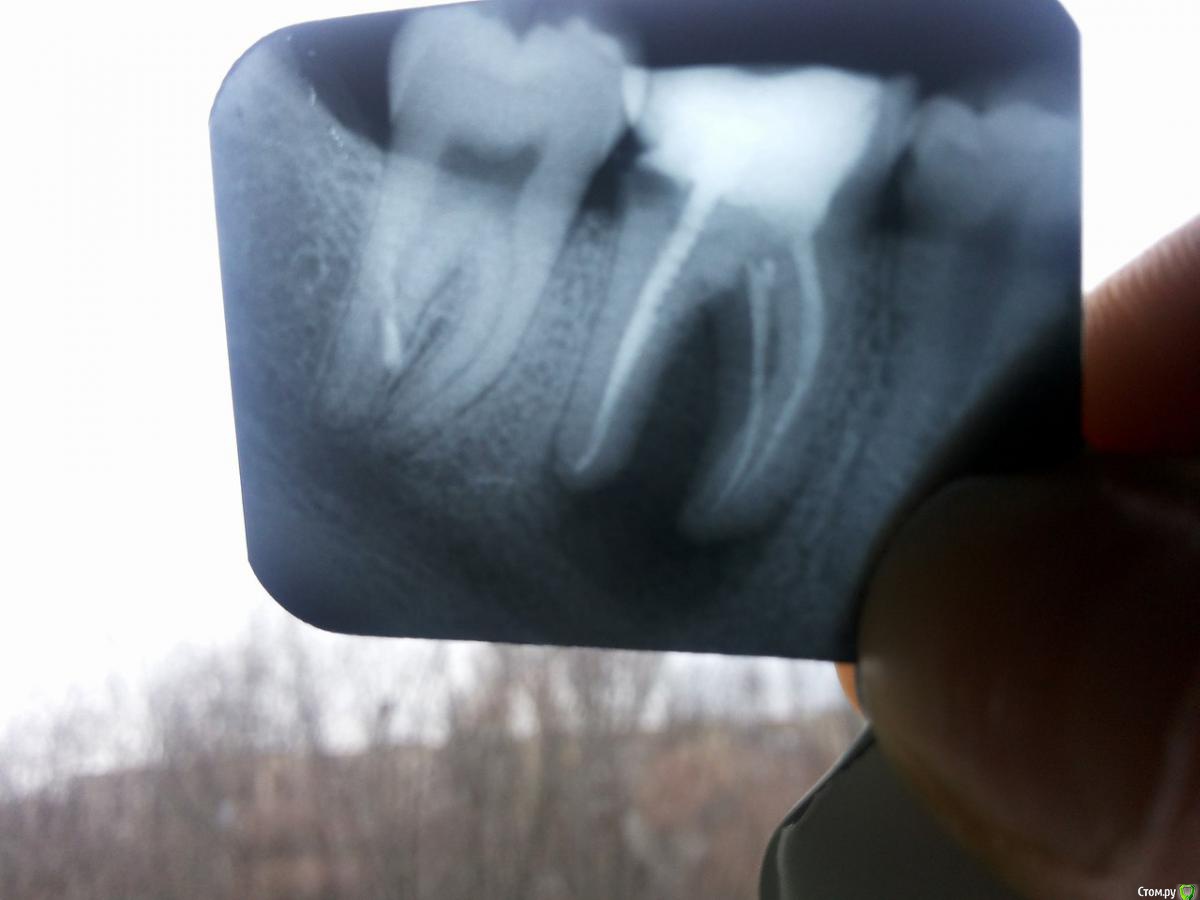

Lilit11 Опубликовано 26 марта, 2016 Поделиться Опубликовано 26 марта, 2016 Здравствуйте. Скажите пожалуйста, зуб подлежит только удалению, или ещё возможно его спасти? Ссылка на комментарий

red_butler Опубликовано 26 марта, 2016 Поделиться Опубликовано 26 марта, 2016 если судить только по снимку, то можно полечить. Но нужен очный осмотр, ревизия и квалифицированный врач. 1 Ссылка на комментарий

horreodor Опубликовано 26 марта, 2016 Поделиться Опубликовано 26 марта, 2016 я соглашусь что нужен очный осмотр, но с моей точки зрения шансы на его спасение очень малы... Ссылка на комментарий

krokomot Опубликовано 26 марта, 2016 Поделиться Опубликовано 26 марта, 2016 Шансы невелики Ссылка на комментарий

Lilit11 Опубликовано 26 марта, 2016 Автор Поделиться Опубликовано 26 марта, 2016 (изменено) Специалисты, объясните пожалуйста, почему его вряд ли получится сохранить, и, почему только удаление?Стоматолог, к которому я обратилась с рентгеном, сказала, что только удаление, и, объяснила это тем, что мой организм воспринимает мой зуб как инородное тело, а дальше я её не совсем поняла, т.к. объясняла она не очень вразумительно. Всё таки не очень хочется остаться без зуба, если есть хоть небольшая возможность, его спасти. Проблема усугубляется ещё и тем, что я не знаю к кому идти. Если здесь есть врачи или пациенты из Днепропетровска, посоветуйте, с кем можно проконсультироваться? Изменено 26 марта, 2016 пользователем Lilit11 Ссылка на комментарий

shishok Опубликовано 26 марта, 2016 Поделиться Опубликовано 26 марта, 2016 Мне кажется или там трещина дистального корня? Ссылка на комментарий